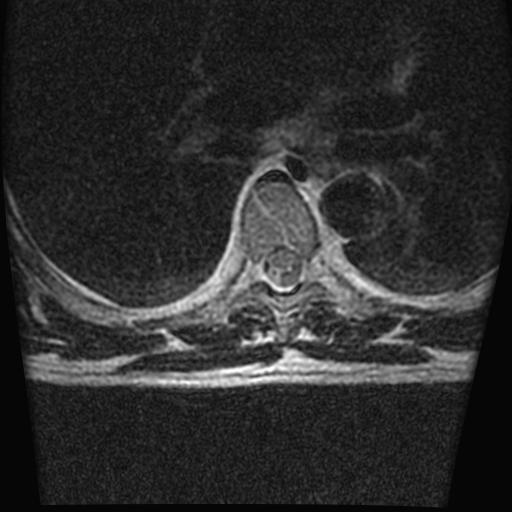

标题: MRI0985:胸椎.68岁男性,胸部疼痛,

68岁男性,胸部疼痛,不适。

t7椎体前1/3信号略减低,椎体上下面凹陷,相应脊髓几周边软组织信号未见改变。考虑:椎体退变。

胸7椎体楔状变形及信号异常,附件未见明显异常信号.椎间隙正常.未见软组织块影.考虑骨质疏松所致压缩性骨折可能大.

胸7椎体楔状变形及信号异常[t1t2 均为低信号],附件未见明显异常信号.椎间隙正常.未见软组织块影.考虑陈旧性压缩性骨折伴退变。

首先需除外单发成骨性转移瘤可能。

转移瘤也不能排除